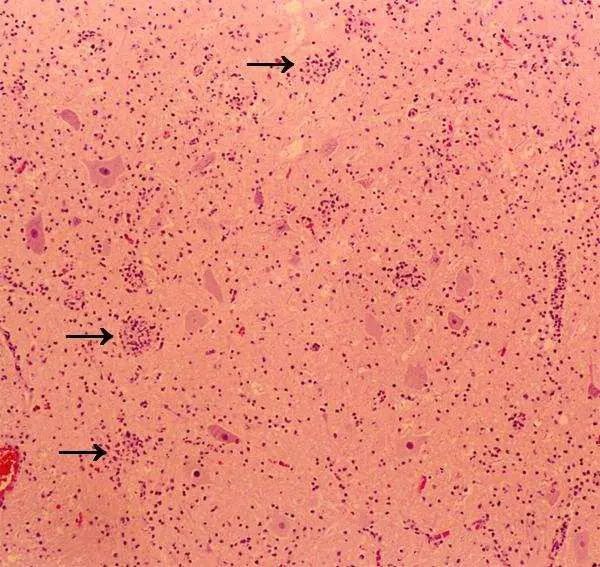

- 組織部位:顯微鏡下可見中樞神經組織的灰質部分。背景為粉紅色的神經纖維網 (Neuropil)。

- 細胞特徵:視野中有數個大型的神經元 (Large neurons),其細胞體碩大、多角形,符合脊髓 前角運動神經元 (Anterior horn motor neurons) 的特徵。

- 病理變化 (箭頭所指):

- 箭頭指向的神經元周圍聚集了大量的小型嗜鹼性細胞(淋巴球、單核球與微膠細胞 microglia)。

- 發炎細胞不僅圍繞神經元,甚至正在侵入並吞噬退化、壞死的神經元細胞體。

- 此為典型的 噬神經細胞現象 (Neuronophagia)。

- 綜合判讀:這是典型的病毒性感染導致前角運動神經元壞死的病理表現,即「脊髓灰質炎」(Poliomyelitis) 的特徵性病變。